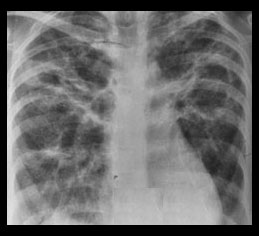

STAGE III STAGE IV

Abnormal lung parenchyma. No lymphadenopathy. ( 15% )